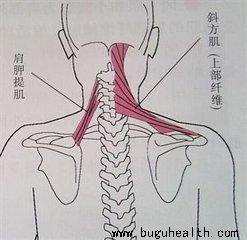

我们举例来讲,上交叉综合征是紧张的背侧的上斜方肌、肩胛提肌,以及腹侧的胸大肌和胸小肌相互交叉,薄弱的前侧的深层屈肌和中下斜方肌相交叉,这时候我们做挺胸抬头的动作时总感觉格外费力,而含胸时则反而轻松了,当我们继续延续这种不正确的体态,就会形成恶性循环,薄弱的肌肉越来越薄弱,紧张的肌肉越来越紧张,当我们想要改善的时候,如果只是去增强薄弱的肌肉,那么就不得不去额外克服紧张肌肉带来的阻力,那么训练效果就会收到影响,所以我们可以先去将紧张的肌肉进行拉伸,那么训练薄弱的肌肉时,肌肉的激活和启动就会更快更省力,就会达到事半功倍的效果了。

关于上交叉,日常的驼背探颈等习惯使得斜方肌上束、斜角肌、胸锁乳突肌紧张,使得颈部压力变大,出现疼痛。